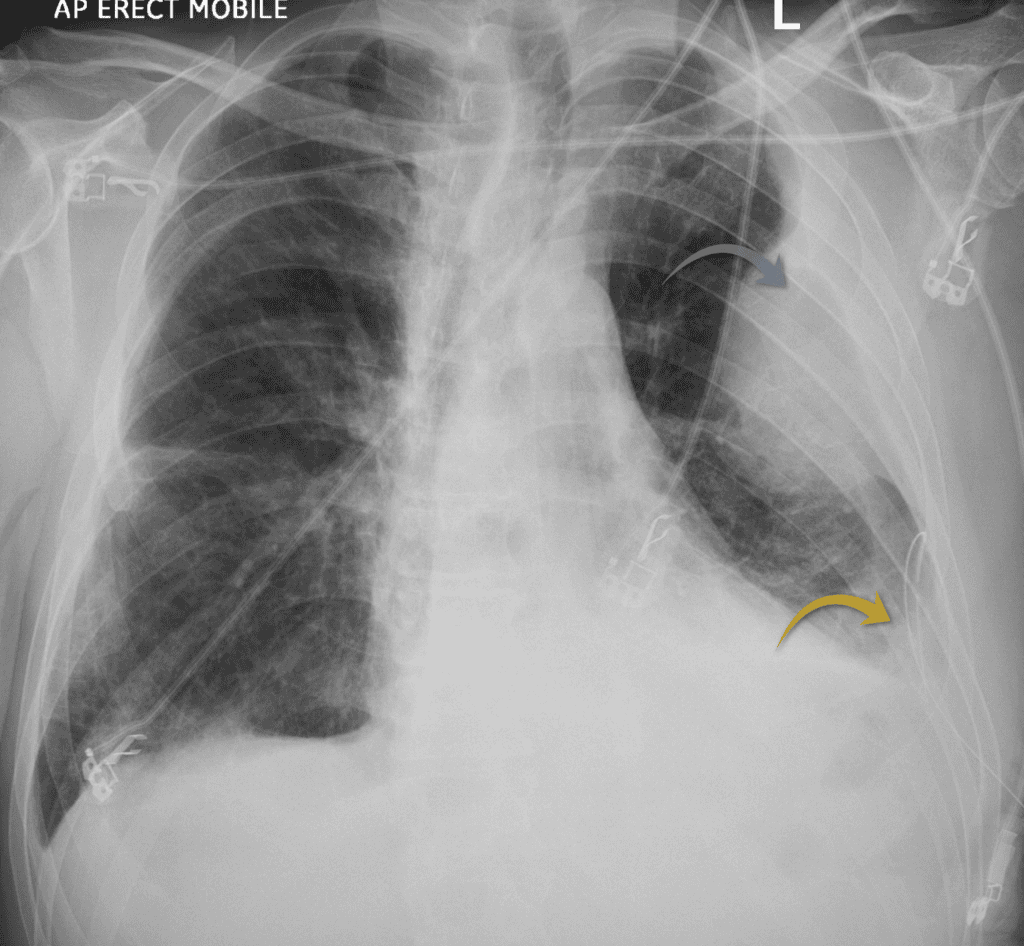

In this case draining the pleural effusion revealed some interesting findings. Have a look at the post drainage X-ray below.

In this case the trachea is deviated to the right, pushed away from the white-out suggesting a pleural effusion

We can see the chest drain is now in place (yellow arrow) and there has been a marked improvement in the white-out and degree of mediastinal shift. There is however now an underlying mass (grey arrow).

This forms obtuse angles with the chest wall suggesting it may be pleurally based. An underlying pleural mass and an associated malignant pleural effusion needs to be suspected at this stage.

Left sided chest drain inserted into the left pleural effusion (yellow arrow) revealing an underlying mass (grey arrow)